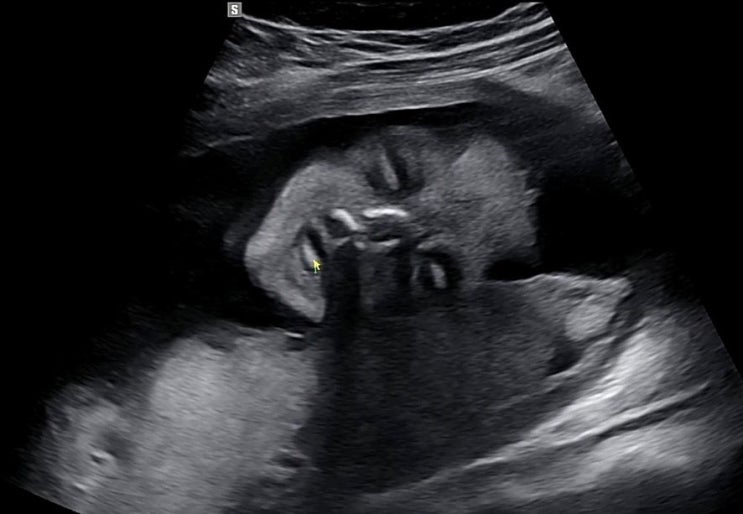

[임신 34주차] 임신 9개월 34주 5일 2.7kg , 임산부 빈혈, 하늘 보는 태아 막달검사 인정병원

안녕하세요~! 34주차 병원에서 막달검사 받고 왔어요!! 막달검사라니.. 벌써 마음이 이상해지더라구요 채혈...

[임신 27주차] 공포의 임당검사, 수치170 임당재검결과 / 입체초음파(인정병원)

안녕하세요~! 으니테이블 입니다!! 날이 더워지면서 숨도 차고 다리 부종도 심해지는 나날들 ㅜㅜ 엄마되는...